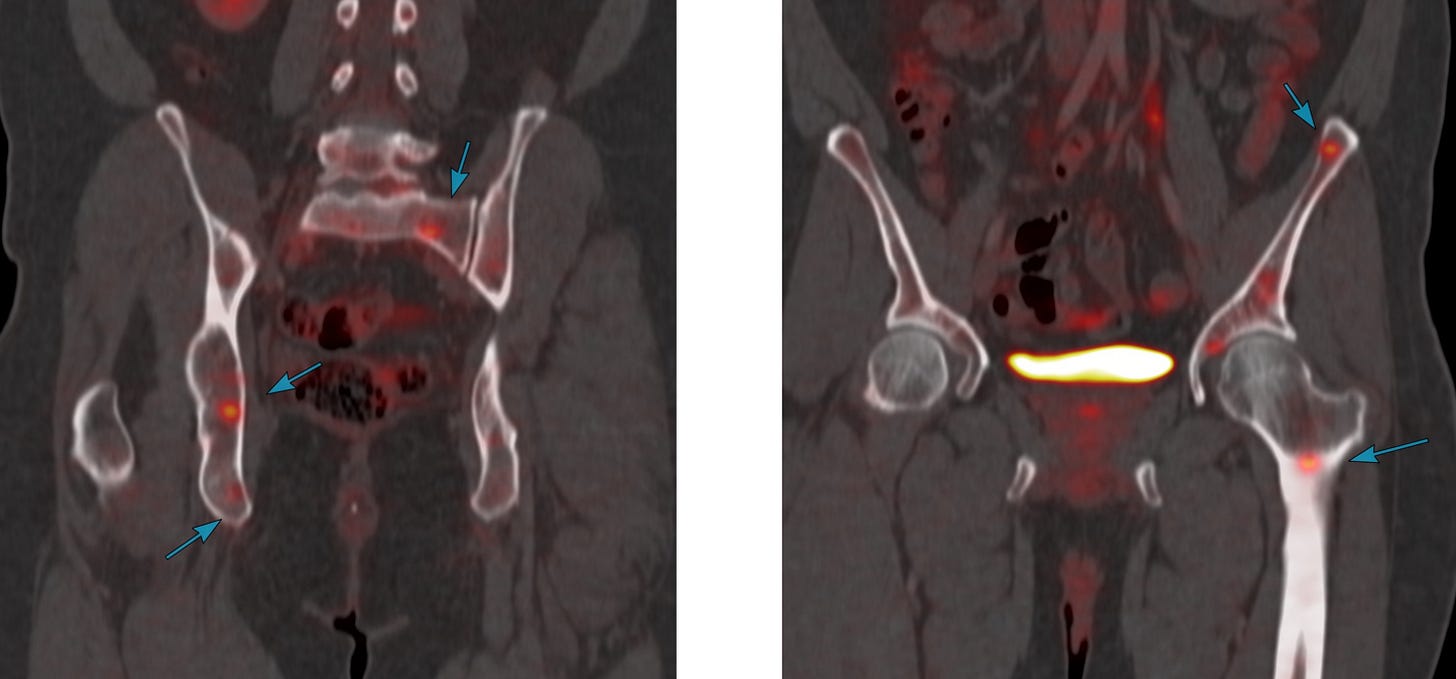

PET/CT showed uptake along with multiple pelvic bone lesions

What do you think is the diagnosis?